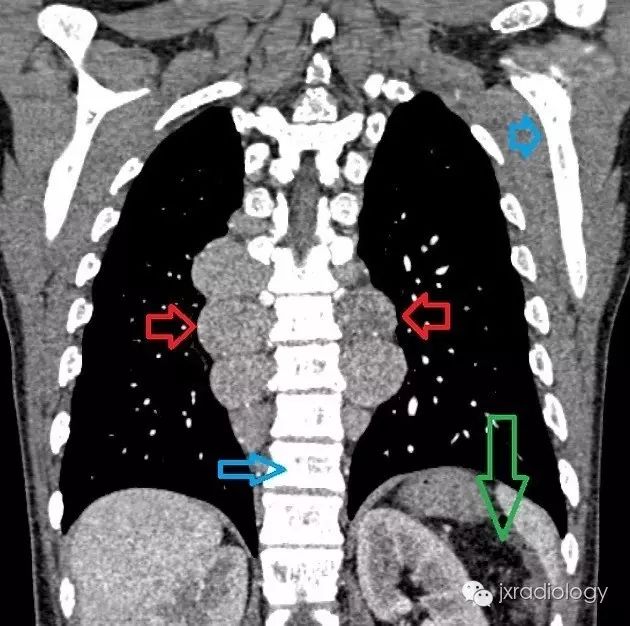

髓外造血器官,影像学上通常表现为器官增大,如超声、CT或MRI上表现为肝肿大、脾大。然而,在不常见的情况下,髓外造血可以发生在胸腔内,呈后纵隔肿块,变现为单侧或双侧脊柱旁肿块,边缘光滑,轮廓分明,常呈分叶状边缘。

(图源:N Engl J Med 2010; 362:253)